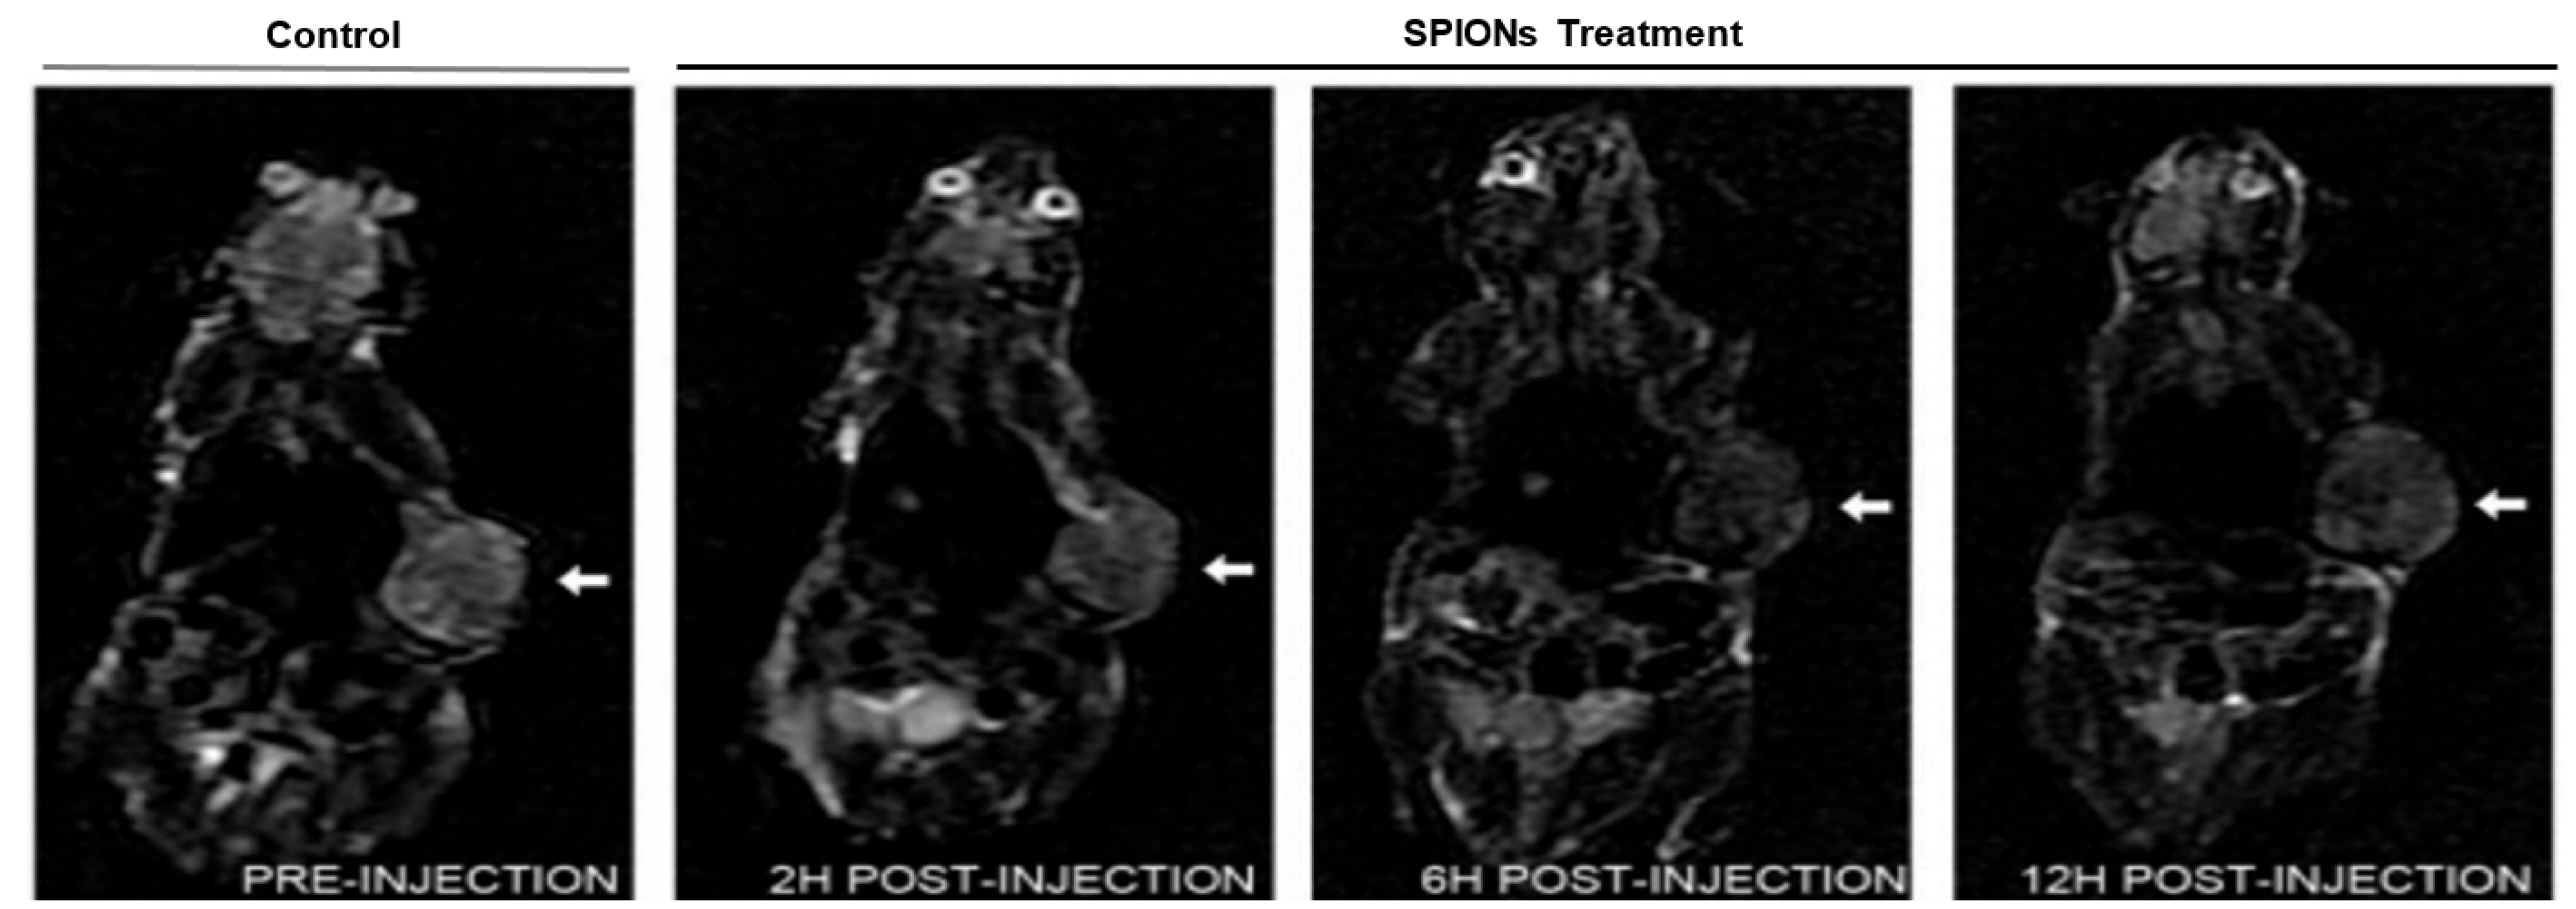

- Sterenczak, K.A.; Meier, M.; Glage, S.; Meyer, M.; Willenbrock, S.; Wefstaedt, P.; Dorsch, M.; Bullerdiek, J.; Murua Escobar, H.; Hedrich, H.; et al. Longitudinal MRI contrast enhanced monitoring of early tumour development with manganese chloride (MnCl2) and superparamagnetic iron oxide nanoparticles (SPIOs) in a CT1258 based in vivo model of prostate cancer. BMC Cancer 2012, 12, 284. [Google Scholar] [CrossRef] [PubMed]